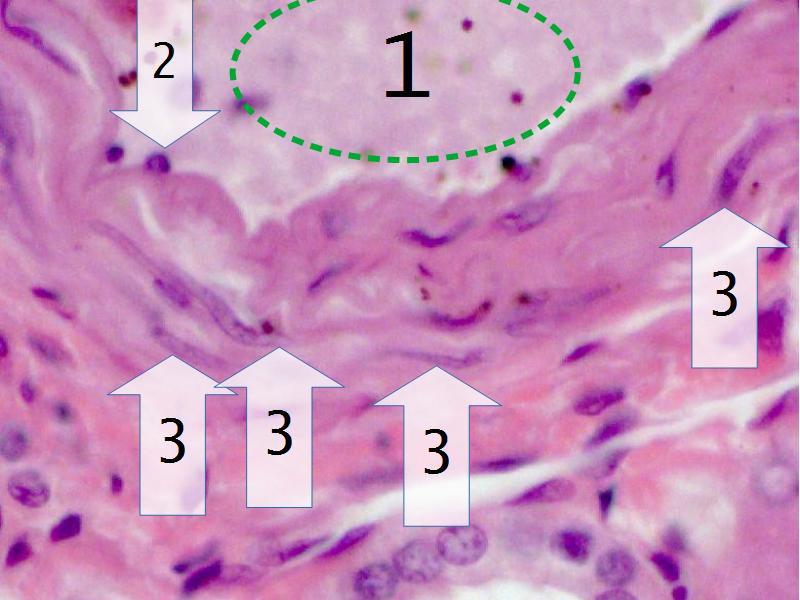

Slides 28 & 76

Kidney: Objectives

- Basic arrangement of nephrons and collecting tubules in the kidney

- Structure of the nephron and collecting tubules

- The renal corpuscle